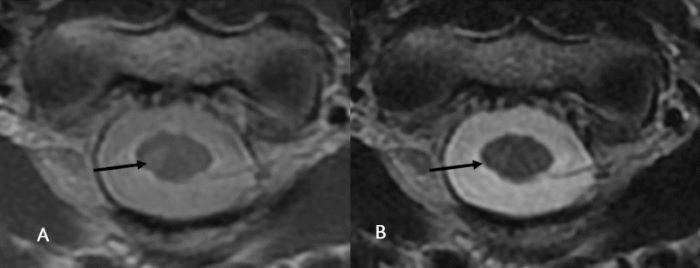

La mediana de la RCR en secuencias ponderadas en DP fue de 5,43 y de 2,97 en secuencias ponderadas en T2, con coeficiente de concordancia de 0,62 (IC95%: 0,48-0,75, SE 0,05 DE 12,25) (►Fig. 1).

Este estudio demuestra que no existe una adecuada concordancia entre las secuencias ponderadas en DP y T2 en el plano axial en términos de número y conspicuidad de las lesiones medulares cervicales en pacientes con EM (►Fig. 2).